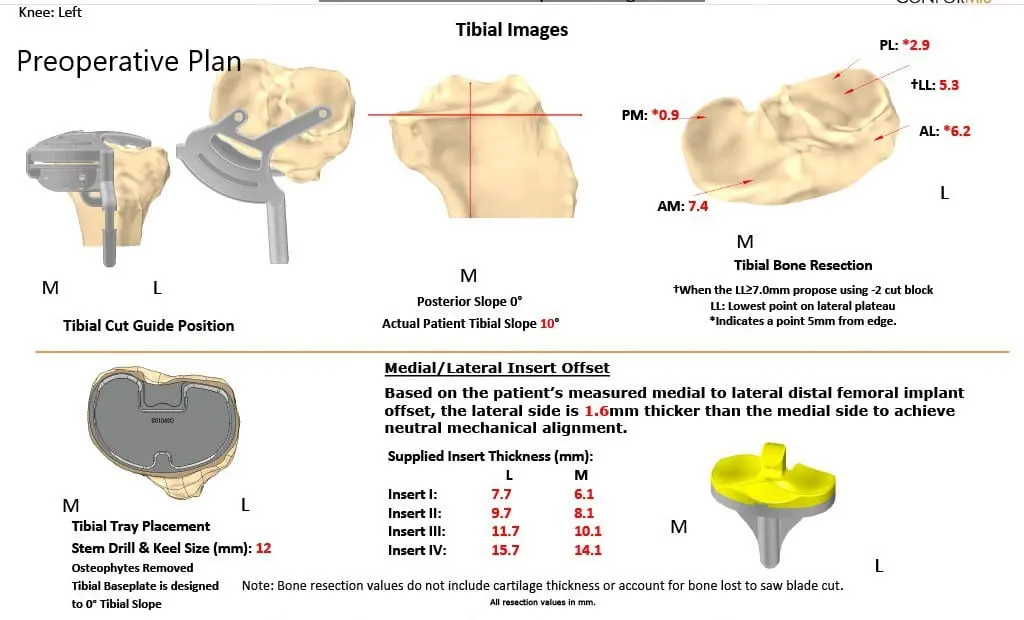

Imaging studies demonstrated medial joint space narrowing with degenerative changes. A CT scan of the patient’s left knee with hip and ankle was obtained a few weeks before the surgery demonstrating tricompartmental osteoarthritis. The data from the CT scan were used to create a 3D model of the patient’s anatomy. The data was then used to create custom implants and custom instruments.

Custom implants and instruments offer surgeons to have perfect alignment and recreation of the joint line before the disease process with bone preservation. A custom patient-specific plan was provided detailing the sizing and cuts of the procedure for accurate alignment. Disposable 3 D printed jigs were to be used designed uniquely for the patient to create bone resection. The details were outlined in a preoperative plan.

Complete Orthopedics patient-specific surgical plan for a left custom knee replacement in a 67-year-old female.